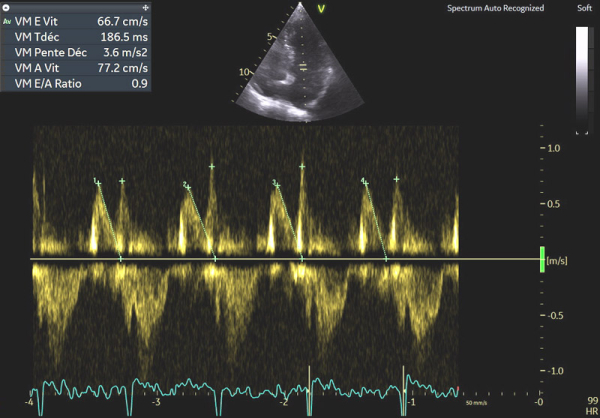

Image 3 : échocardiographie, flux Doppler pulsé transmitral

En cas d’atteinte précoce d’amylose cardiaque, ce sont en effet les premières anomalies à pouvoir être objectivées et il peut ne pas y avoir encore d’altération marquée du SLG (cf Image 7), de signe de dysfonction diastolique VG (cf Images 3 et 4), de dilatation de l’OG (cf Image 8), de dysfonction systolique du VD (cf Image 5) et les pressions peuvent être normales.